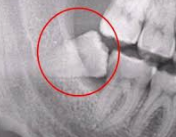

사람의 턱은 크기가 한정되어 있기 때문에 수용할 수 있는 치아의 갯수가 한정적입니다. 턱이 발달되고 큰 사람들은 사랑니가 자라나도 정상적으로 자라나 문제가 없을수도 있지만 사랑니가 자라는 대부분의 사람들은 수용할 수 있는 치아의 갯수가 초과되기 때문에 치아가 자라날 자리가 없어 잇몸을 비집고 자라거나 잇몸안에서 나오지 못하는 경우가 대부분 입니다.

그렇기 때문에 어금니 신경을 건들여 통증이 있고 좁은 잇몸을 비좁고 나오려고 하기 때문에 붓는 증상이 나타나게 됩니다.